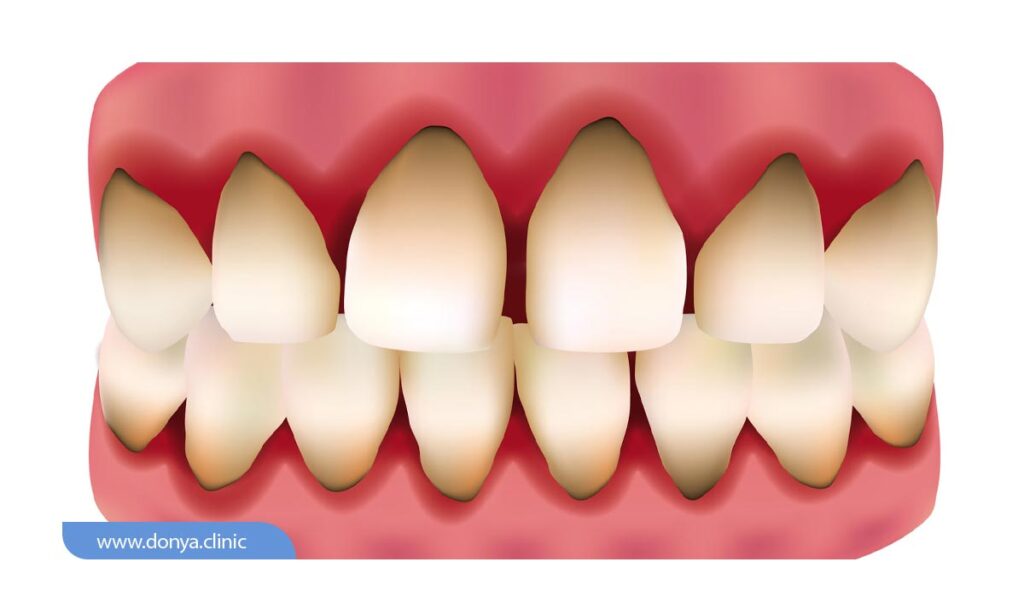

تحلیل لثه یا (Gum recession) نوع رایجی از مشکلات دندانپزشکی است که در آن، حاشیه بافت لثه (که دندان ها را احاطه کرده) از بین رفته یا نازک می شود. اصطلاحاً به این مشکل عقب نشینی لثه نیز گفته می شود. زمانی که لثه تحلیل می رود، ریشه دندان ها نمایان می شود و مشکلات زیادی برای افراد ایجاد می شود.

اولین علامت عقب نشینی لثه معمولاً حساسیت دندان است. به جز این ممکن است متوجه شوید ریشه دندان در معرض دید قرار گرفته یا طول دندان کمی بیشتر از چیزی شده که قبلا بود.

تحلیل لثه، که به آن عقب نشینی لثه نیز گفته می شود، وضعیتی است که در آن لثه ها شروع به کوچک شدن و عقب نشینی از دندان ها می کنند. این می تواند منجر به بیرون زدگی ریشه دندان ها شود و در صورت عدم درمان، به بیماری های جدی دهان و دندان منجر گردد. در اینجا برخی از علائم و نشانه های رایج آن آورده شده است:

- منقبض شدن مشهود لثه ها که در آن لثه ها به نظر کوچک تر و دندان ها بلندتر به نظر می رسند.

- مشخص شدن ریشه های دندان که توسط لثه پوشیده می شوند.

- سطح حساسیت پذیری دندان ها به تغییرات دمایی و اعمال فشار افزایش می یابد.